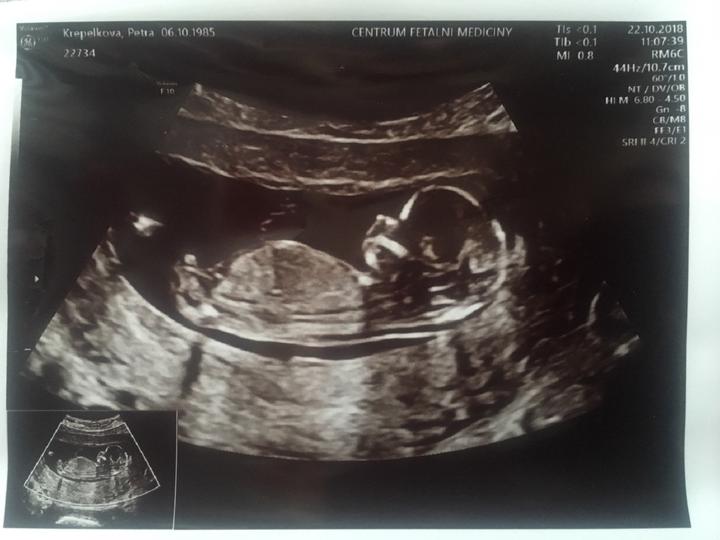

Ortel lékařů zněl: Přirozeně mít děti nebudete. Teď čekáme třetího zdravého chlapečka😍 1. po ivf, 2. přirozeně na druhý pokus a 3. ani nevím jak❤️ Manžel si už potřetí přál holčičku, ale asi jsou nám souzeni samí chlapáci🙂